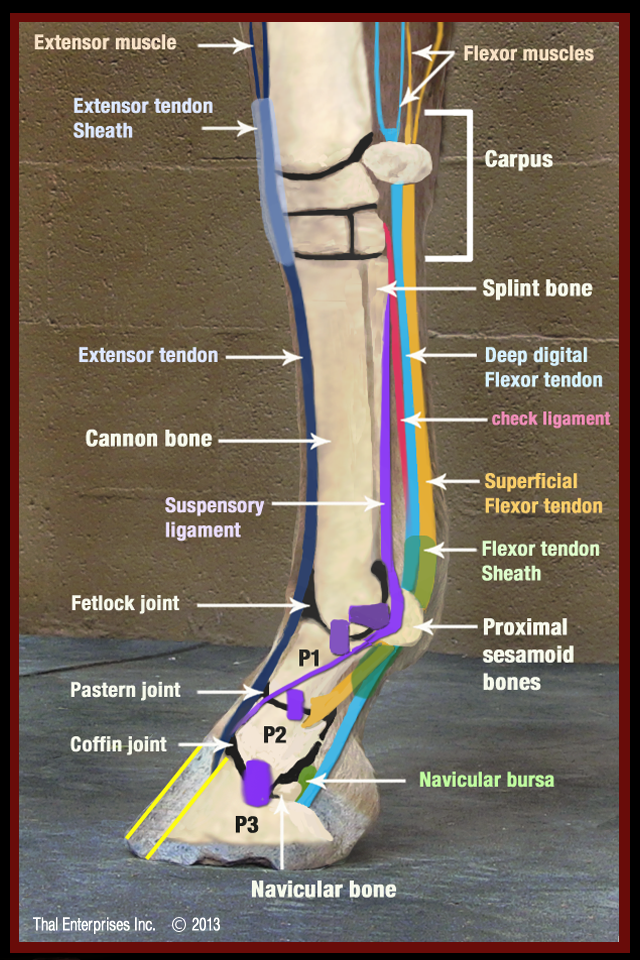

The important anatomic structures of the lower limb of the horse, seen from the side.